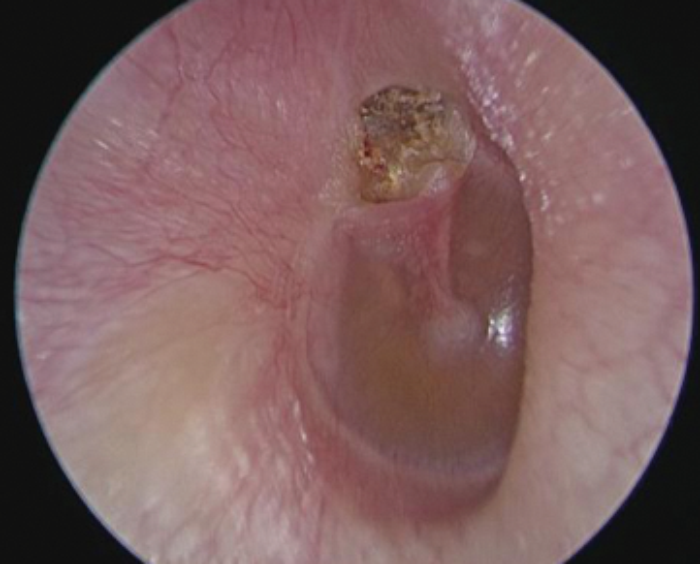

During microscopic surgery, the field of view is limited by the narrowest segment of the ear canal. The use of an endoscope allows one to easily bypass the narrow segment and look beyond without excising healthy tissue for exposure (Figure 3). An anterior perforation can therefore be repaired entirely transcanal with an endoscope, without the postauricular incision and canaloplasty often required with microscopic techniques.

Figure 3: Narrow microscopic (top) versus wide endoscopic (bottom) view.